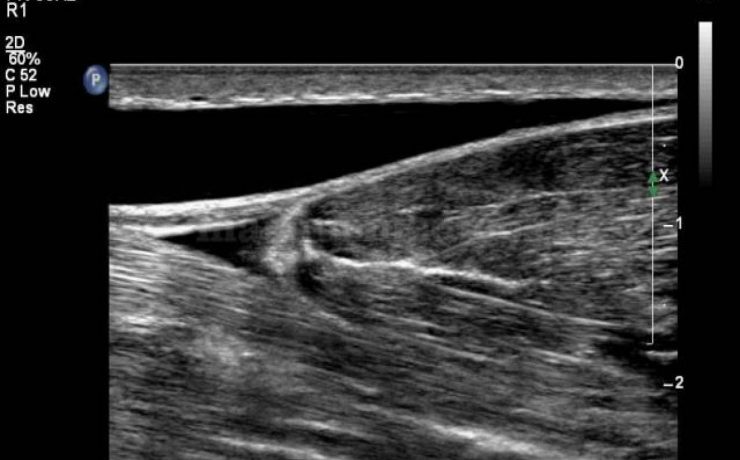

Más del 95% de las enfermedades biliares, son debidas a colelitiasis. En Estados Unidos su costo anual asciende a 8 millones de dólares, el 40% de los mayores de 40 años tiene colelitiasis y10 a 30% presentaran síntomas. 11% de la población adulta de E.U.A. Tiene cálculos biliares y esta